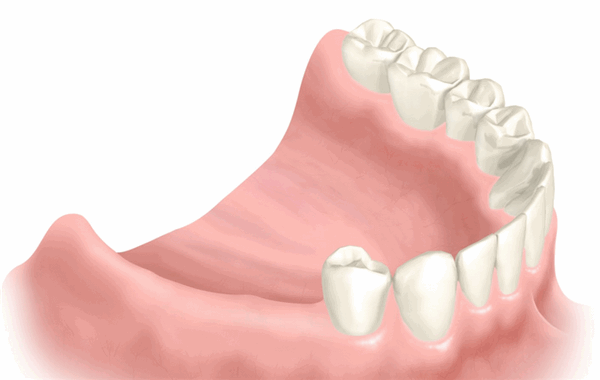

Подготовка к протезированию несъемными мостовидными протезами

Установка моста на опорных единицах зависит от их состояния. Если зубы живые, необходимо:

- депульпировать (удалить нерв);

- запломбировать каналы;

- сточить эмаль;

- снять слепок;

- установить коронку.